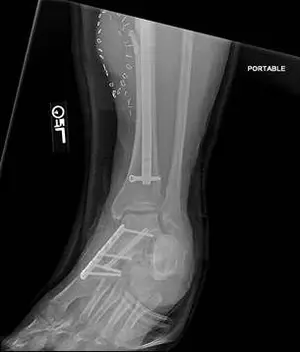

These are pics of an open midfoot fracture and dislocation after a motor vehicle accident.

These are pics of the external fixator on to hold temporary reduction prior to internal fixation

These are pics of the plate and screws stabilizing the fractures after ex fix was removed. An IM rod was also placed for a tibia fracture.